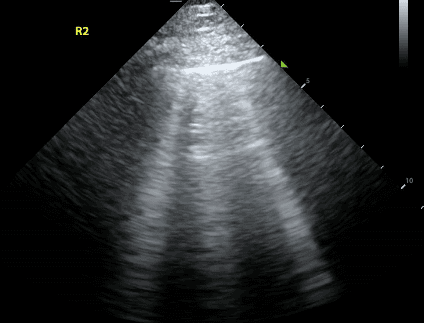

The rapid response team nurse receives a call for a septic patient who has a low blood pressure. The patient has already received one liter of IV fluid but given the patient’s history of heart failure, the team is hesitant to give further fluids. The patient is not requiring oxygen and does not appear to have any trouble breathing. The nurse orders a portable chest x-ray to check for signs of fluid in the lungs.

With bedside ultrasound, the nurse could quickly identify if the patient had B-lines - a sign that is pathognomonic for fluid in the lungs. In the absence of B-lines, the team would feel more comfortable giving IV fluids to address the patient’s low blood pressure.